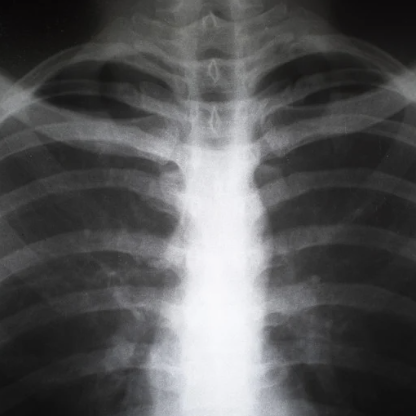

Respiratory Conditions and Chest X-Rays

If you are experiencing persistent coughing, difficulty breathing, or chest pain, a chest X-ray may be needed to evaluate your lung health. Our imaging services can detect pneumonia, bronchitis, tuberculosis, and other respiratory illnesses, allowing for prompt treatment and management.

X-rays are a form of electromagnetic radiation used to create images of the inside of the body. They are an essential diagnostic tool that helps medical professionals assess bones, organs, and tissues without invasive procedures. By passing small doses of radiation through the body, X-rays produce images based on the varying densities of structures within. Dense materials such as bones appear white on the image, while softer tissues appear in shades of gray, allowing providers to identify abnormalities effectively.